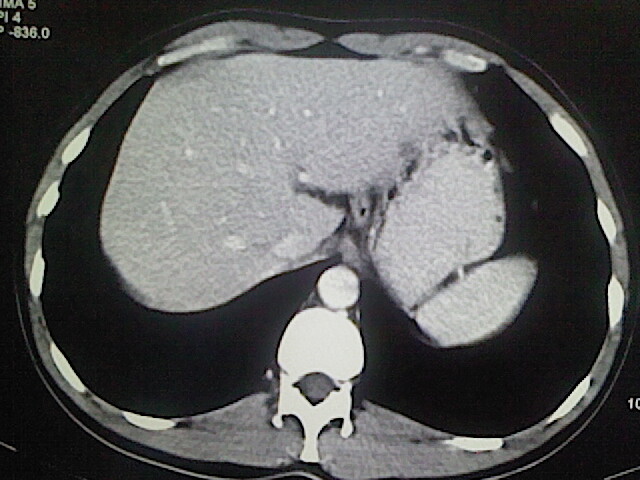

以下是引用卜一在2009-3-14 9:49:00的发言:[br]胆囊萎缩,胆囊壁不规则增厚,内部结构模糊,增强明显强化。另:肝左叶外侧段肝囊肿。支持:慢性胆囊炎!高度可疑:胆囊癌!

以下是引用余辉在2009-3-14 8:48:00的发言:[br]1)慢性胆囊炎。2)肝左叶外侧段肝囊肿。3)脂肪肝。[br]支持,胆囊萎缩,密度增高,不知b超具体有何提示,钙胆汁?结石?

以下是引用jiangjing在2009-3-14 10:18:00的发言:[br]1)慢性胆囊炎。2)肝左叶外侧段肝囊肿。3)脂肪肝。4.】建议行肝功能检查